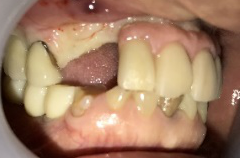

女性Mさん 40代(インプラント)

主訴

下、左右歯がないところに歯を入れたい。

治療内容

右下に2本、左下に1本インプラントを入れました。

所感

下顎左右奥の歯がないところに、インプラント治療を希望されて来院されました。X-Guideを使用し埋入しました。治療後「左右の奥歯でしっかり噛めてうれしいです。」と、とても喜んでくださいました。

インプラント3本:¥363,000×3本=¥1,089,000(税込)

Before

After